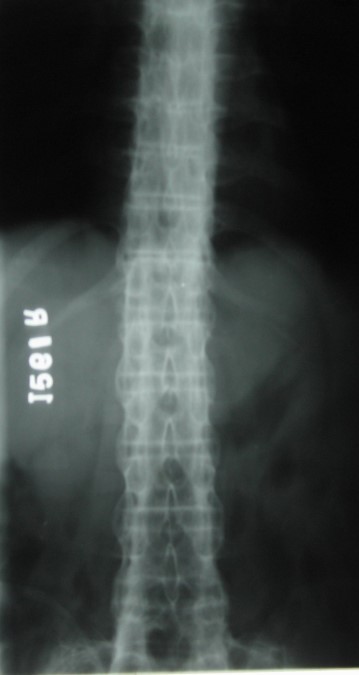

Lumbar Spine A.P – middle aged male patient